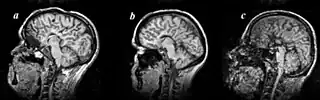

| MRI images of three patients in the sagittal plane. A and B: Complete agenesis of the corpus callosum. C: Complete agenesis of both the corpus callosum and the anterior commissure. | |